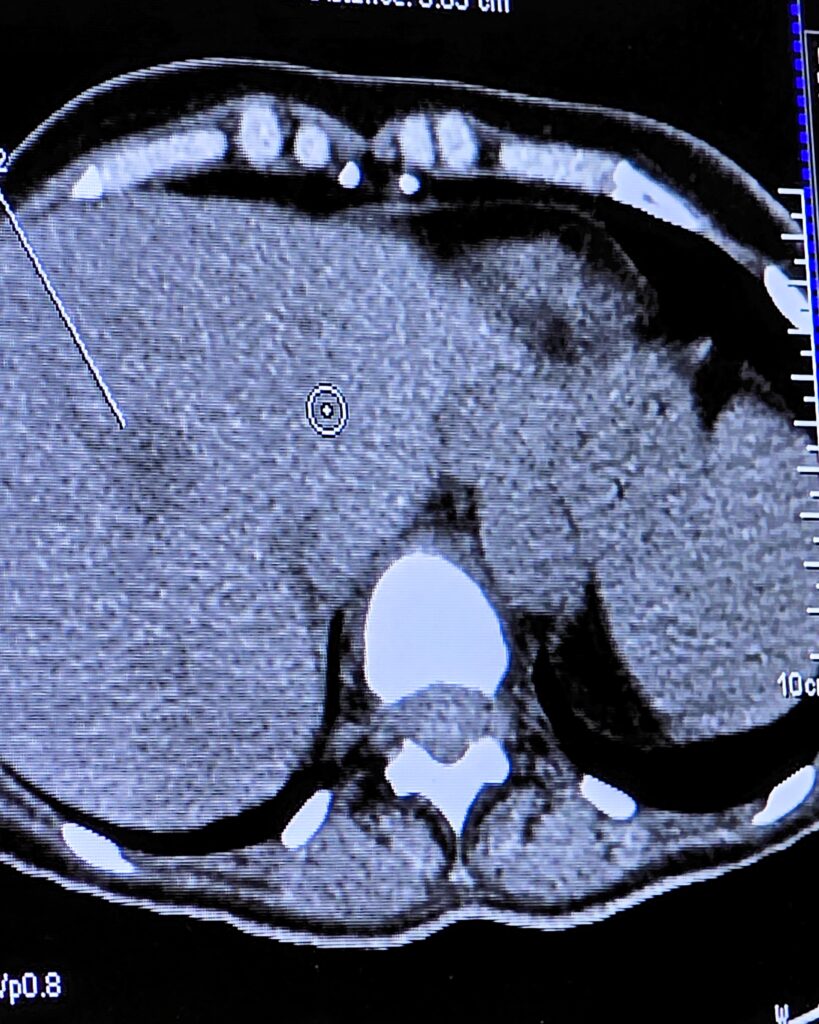

Mikrovlnná ablácia umožňuje zničiť nádor priamo na mieste – pomocou tepla, bez klasickej operácie.

👉 Presnosť, ktorá rozhoduje